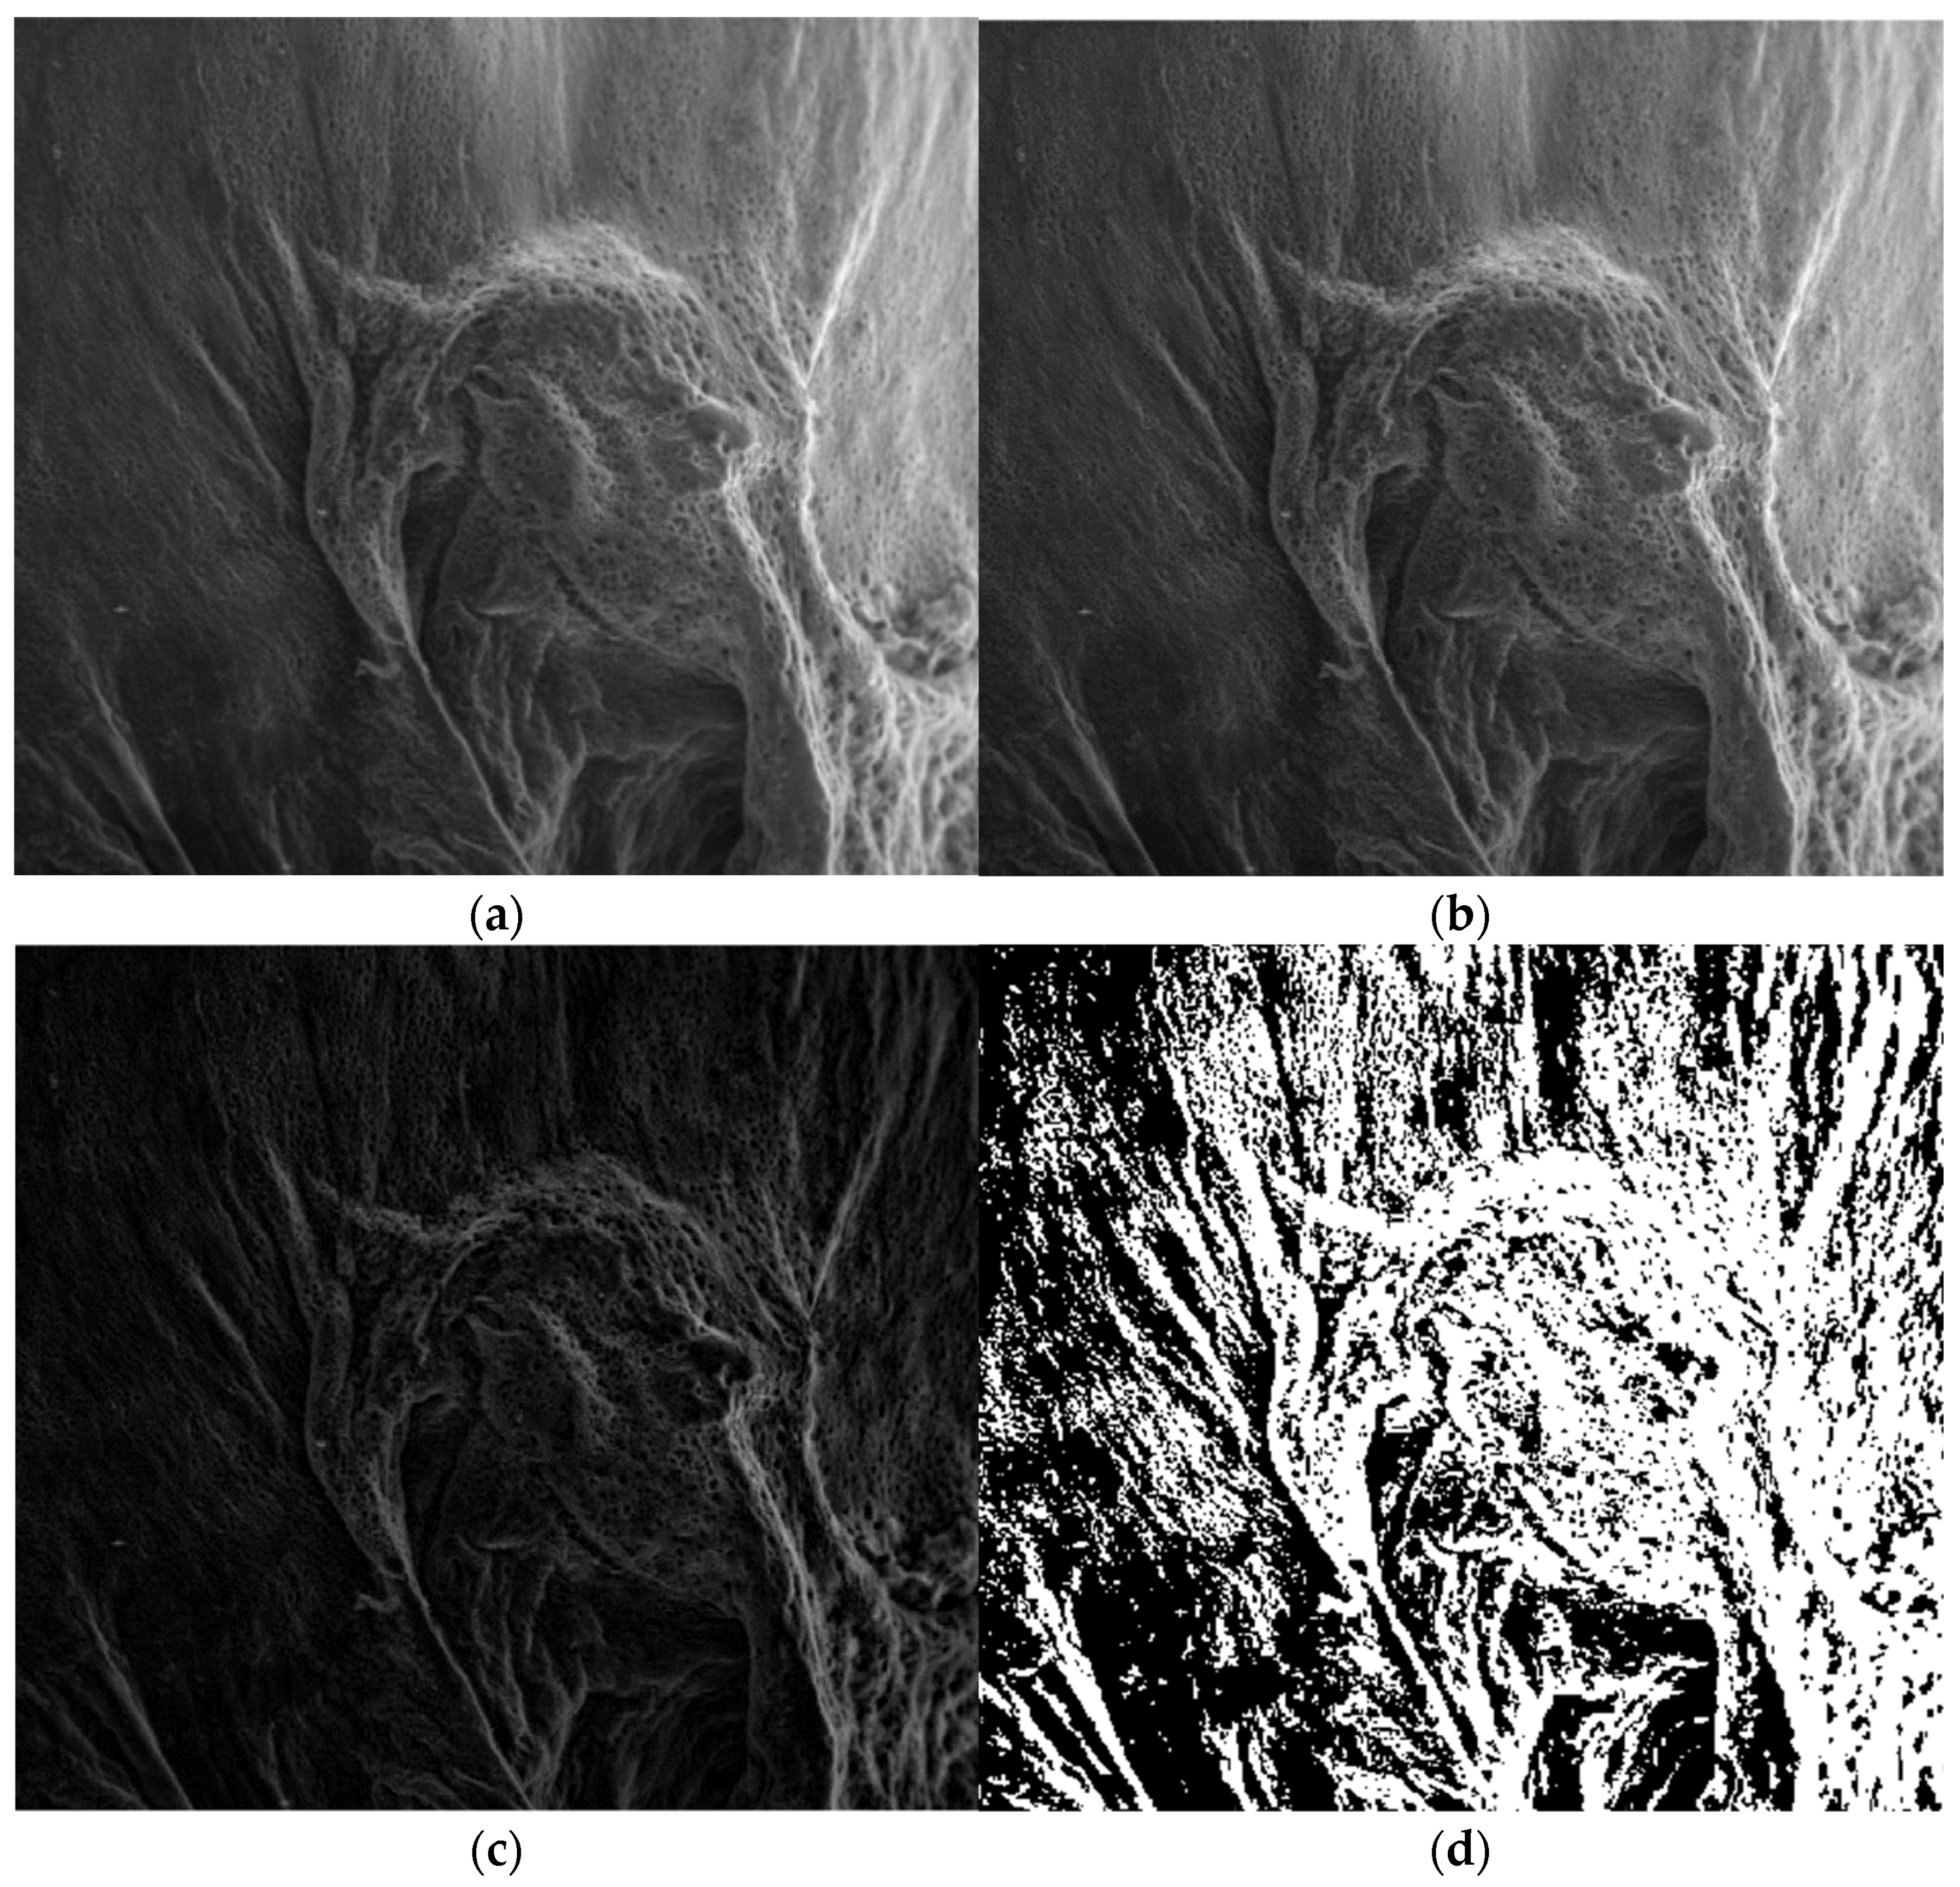

| Name | Fractal Dimension | Standard Deviation | Lacunarity |

|---|---|---|---|

| Image P1 | 1.8621 | 0.0733 | 0.0385 |

| Image P2 | 1.8837 | 0.0894 | 0.0498 |

| Image P3 | 1.8561 | 0.0702 | 0.0324 |